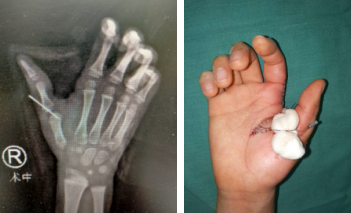

4月9日,朱主任手术团队为涛涛进行了右拇指关节内固定、虎口开大、带蒂筋膜皮瓣、韧带松解修复等一系列矫形手术。手术全程不到3小时,术后涛涛恢复良好。

术中(左)术后即刻(右)

朱主任介绍,涛涛的右拇指外形和功能术后较前将会获得较大改善,后期仍需再配合康复锻炼,后期手指可张开,完成日常的一些拿捏动作。